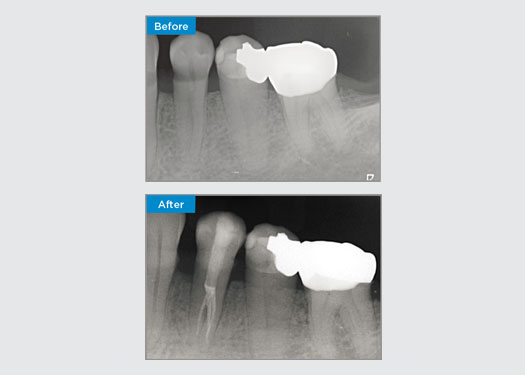

Casos clínicos

Los médicos de todas partes de Australia y Nueva Zelanda comparten amablemente presentaciones relevantes, interesantes y, a veces, desafiantes para los pacientes, junto con su selección de materiales y métodos para optimizar los resultados de sus pacientes.

En Dentsply Sirona, cada día destacamos a profesionales dentales de todo el mundo para que brinden a millones de pacientes un mejor cuidado dental y hagan sonreír a las personas. Nuestro enfoque de caso clínico se trata de compartir estas sonrisas, que los médicos de Australia y Nueva Zelanda han creado, con la comunidad dental en general.